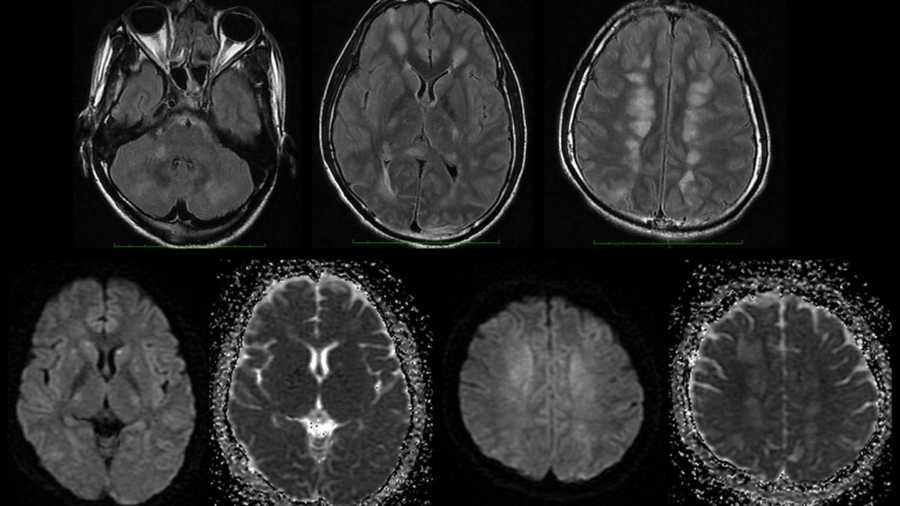

An 11-year-old female presented with complaints of progressive weakness of the left upper and lower limbs for 1 year, dysphagia for 4 months, reduced vision in the left eye for 3 months, dysarthria for 2 months, and urinary incontinence for 15 days.